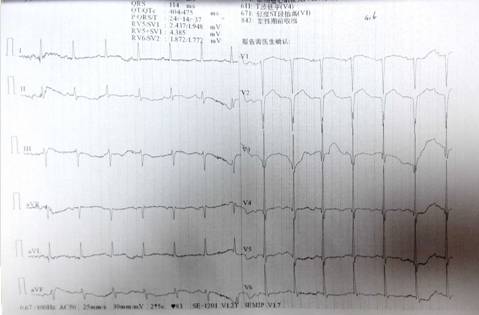

现病史:患者亲人代诉患者7天前突发胸闷、胸痛,其症状呈胸骨中下段压榨感,持续未缓解,无肩背部放射痛,不伴出汗,无头晕、恶心、反酸、嗳气等不适。遂立即至“新宁崀山医院”就诊,途中含服硝酸甘油症状未缓解,经心电图检查提示“1.窦性心律 2. 急性前壁心肌梗死 3.肺型P波 4.左室面高电压5.ST-T改变 肌钙蛋白示微阳性”,诊断冠心病,急性前壁心肌梗死,心功能III级,立即予以溶栓术(尿激酶150万U),术后予以抗凝、扩血管、降压(具体用药不详)后,患者症状较前稍好转。2天前患者开始出现咳嗽、咳痰,痰中带血,色鲜红,量不多,无血凝块,胸闷、胸痛较前好转,夜间有阵发性呼吸困难,无头晕、头痛,无恶心、呕吐、无黑便等症状;伴咽痛,为求进一步诊治,遂至我院急诊就诊,诊断为“1.冠心病 急性前壁心肌梗死 心功能III级(killip分级)溶栓术后 2.肺部感染 3.支气管扩张 4.高血压1级 高危组”,予以莫西沙星抗感染、前列地尔改善循环、泮托拉唑护胃、硫酸氯吡格雷片抗血小板后,患者症状稍缓解,为求进一步诊治,急诊以“冠心病 急性前壁心肌梗死 心功能III级(killip分级) 溶栓术后”收入我科。